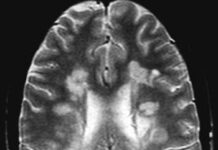

La Esclerosis Múltiple

Cualquier persona que sufra de esclerosis múltiple sin importar su discapacidad necesita realizar ejercicio de manera regular, es importante tener claro que el ejercicio...